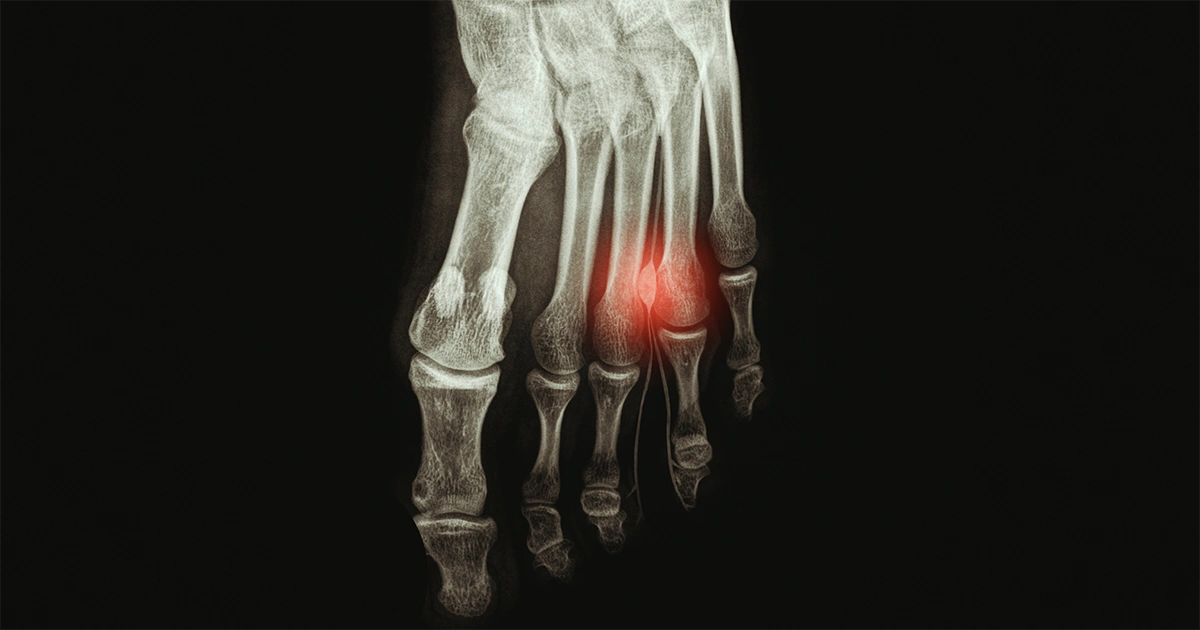

Ortopedista e Traumatologista especialista em pé, tornozelo e joelho